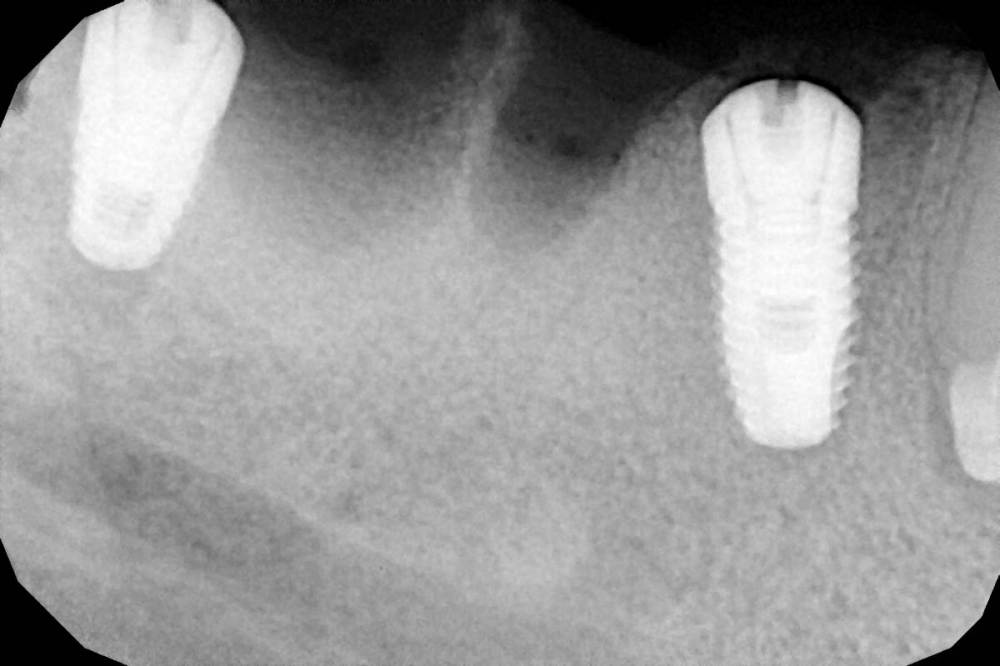

Поставил фдм, без как-либо пластик.

Коллеги, как вы "ищите" свои импланты? и какими методиками чаще проводите раскрытие?

IMG_5708.thumb.jpg.bcd7acfc5f85c68bfd680783369434ba.jpgIMG_5710.jpg